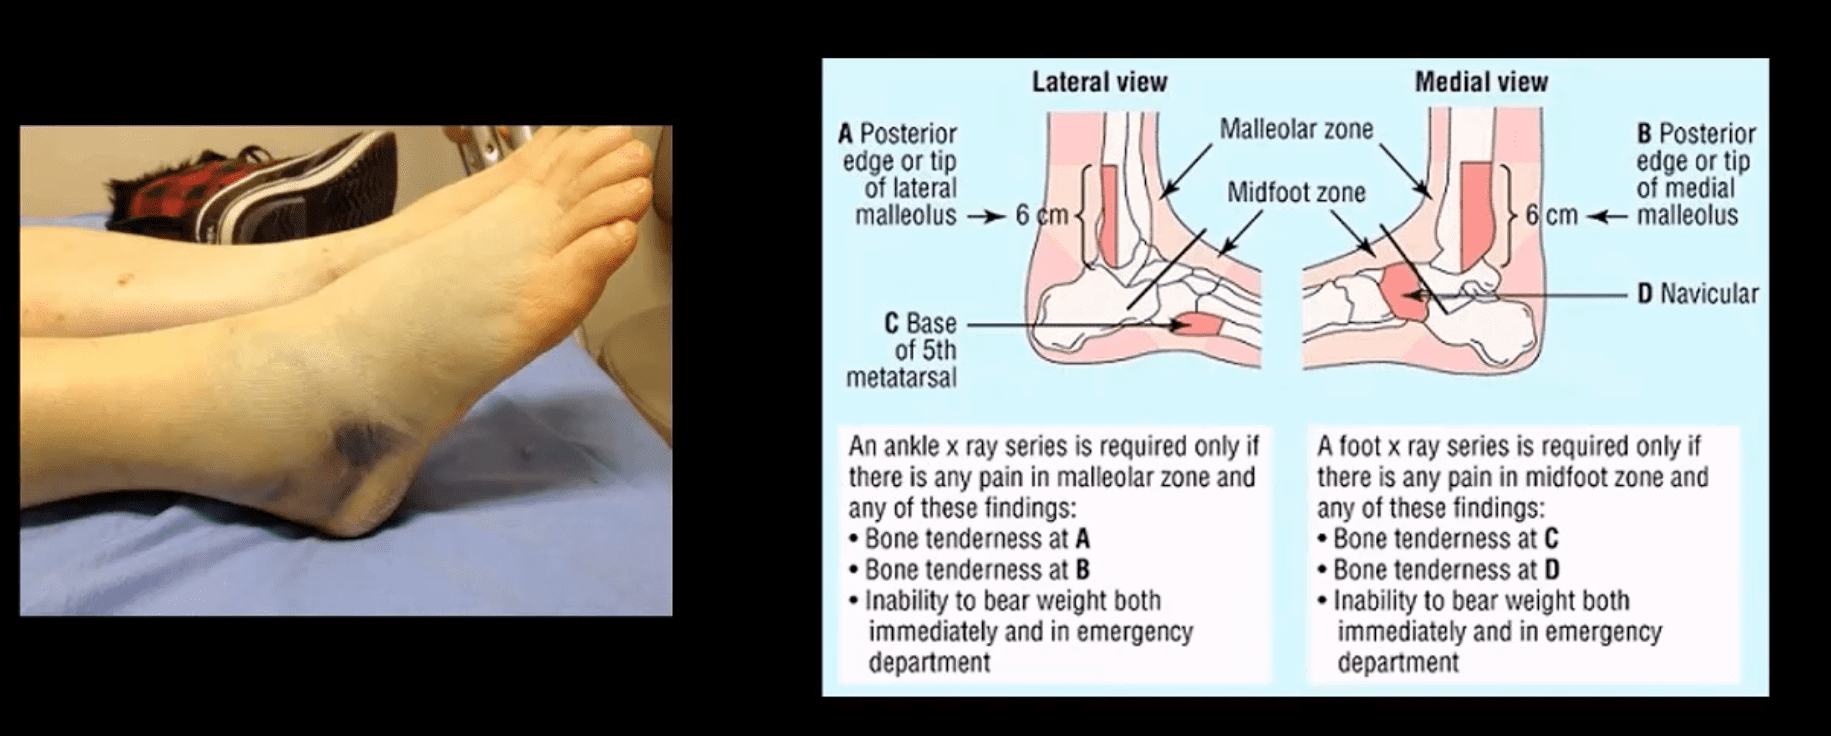

Clinical Dx Accuracy

- Ankle Fractures could be facilitated by the “Ottawa Rule“